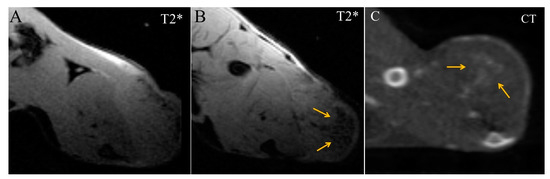

2. Results